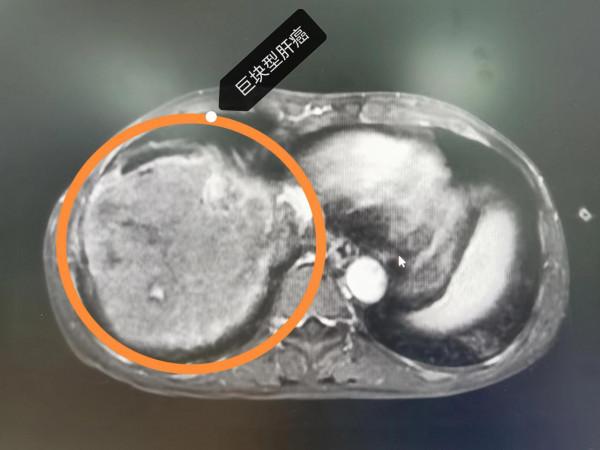

晚期肝癌的病人也不要輕易放棄!近2-3年,晚期肝癌的治療獲得了較大的突破,介入治療+靶向藥+PD1的治療組合,大部分情況下可以取得不錯的治療效果。這是一例非常晚期的肝癌病人,這要是在2-3年前,估計就是勸病人回家,該吃吃該喝喝,預計不會超過3個月的生存期。本例患者巨塊型肝癌合併下腔靜脈癌栓(下腔靜脈幾乎完全堵塞並臨近心房口了)及門靜脈主幹及右支癌栓的病人,經過2次的介入治療(肝動脈灌注化療術(HAIC)後,病灶明顯的縮小,癌栓明顯的消退,腫瘤指標直線下降,整個人的精神狀態持續好轉,未來可期。